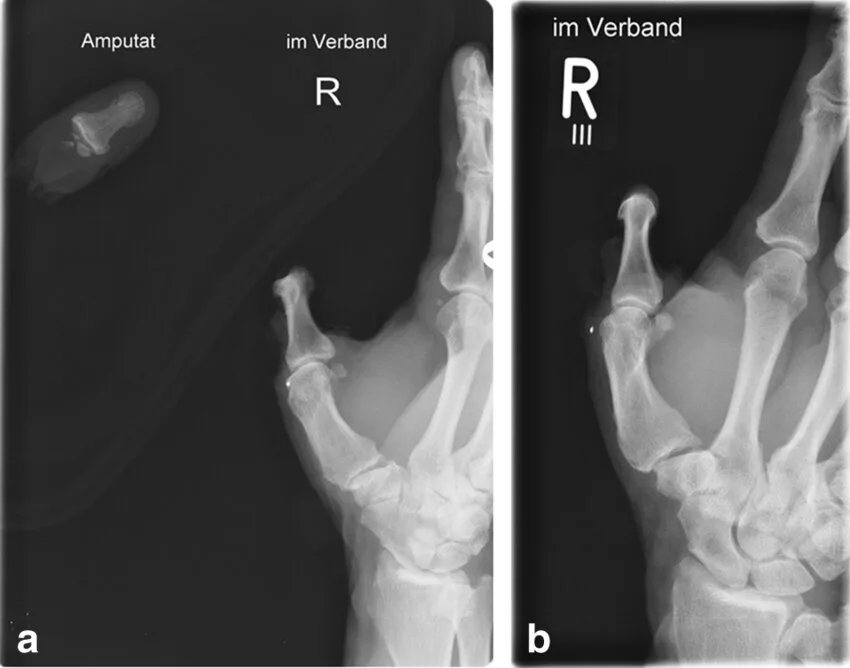

This is ring avulsion injury (often called degloving when severe), and it’s every trauma surgeon’s nightmare. The ring catches on something immovable, and the body’s forward momentum yanks the soft tissues—skin, tendons, nerves, blood vessels—right off the bone like a glove being pulled inside out.

Even if the finger stays attached, the damage can be devastating. Blood flow gets cut off instantly, swelling turns the ring into a tourniquet, and without immediate intervention, tissue dies.

Warning: The next images show real medical examples (post-injury fingers and X-rays). They’re graphic but illustrate why this is so serious.